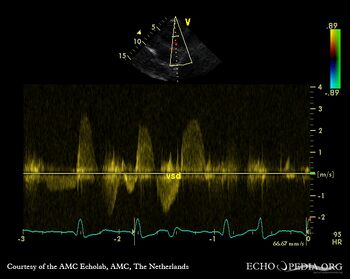

Apical VSD

Courtesy of: AMC Echolab, AMC, The Netherlands

A4CH: Apical VSD, bidirectional shunt Continuous-wave signal